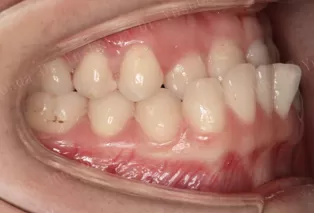

Intraoral photos